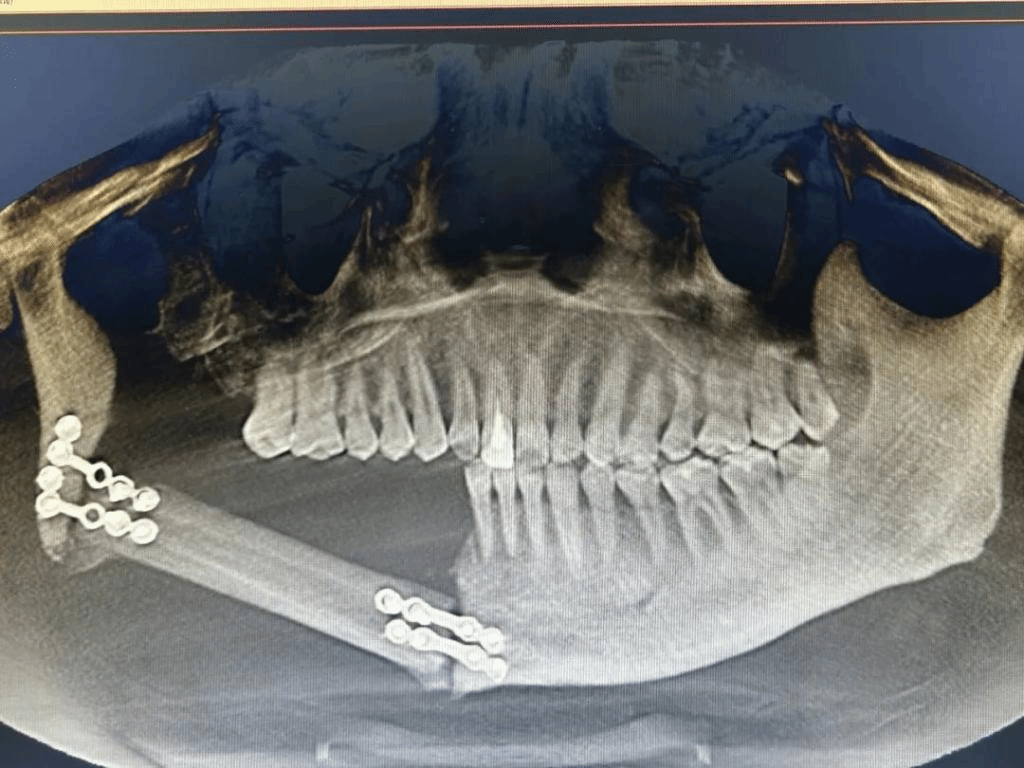

经导航拟定种植方案(左)种植术后影像(右)

相比于传统定位技术,5G数字化动态导航能够更精准的判断最佳种植位置和方向,缩短手术时间,降低安全风险。经过对患者口腔颌面锥形束CT影像的测量,团队确定了手术方案,在5G数字化动态导航下在患者右侧下颌腓骨体突破双皮质层,精确植入3枚种植体,全部初始扭力合格稳固。不到一小时即完成手术,植入位置与导航设计完全一致,术后患者无明显出血、肿胀、疼痛等不良反应,复查种植体在位,无脱落迹象。